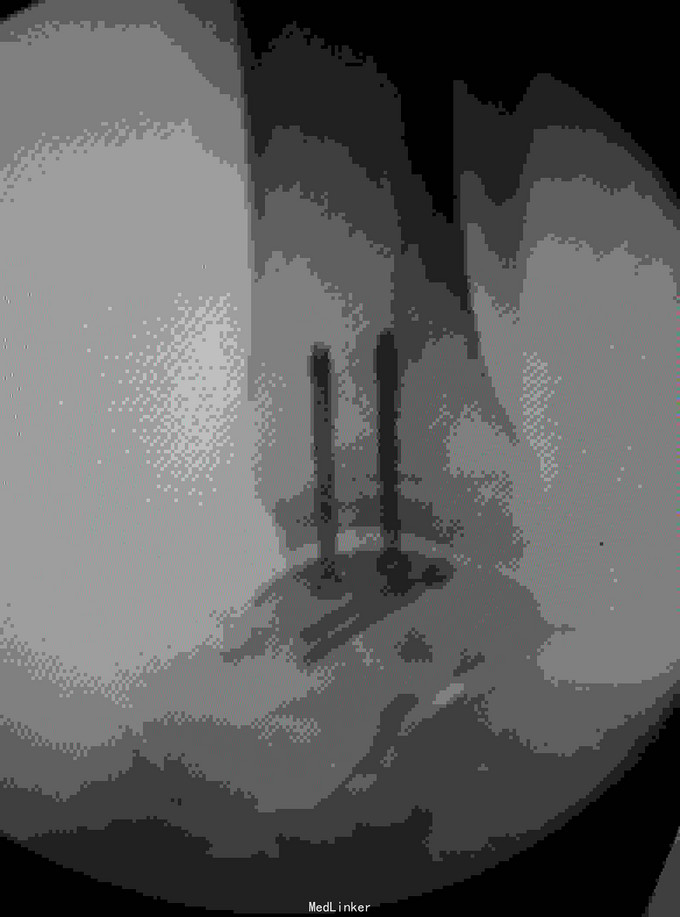

诊断是右距骨粉碎性骨折。给予行内踝截骨显露骨折端进行复位,采用Herbert钉进行固定。

术后复查X线片提示骨折端完全复位,内固定固定在位良好。 讨论:距骨骨折的主要并发症是坏死,骨不愈合等,但近年来随着对其认识的不断明确,治疗比较规范,积极的进行切开复位,并行坚强固定,近年的研究报告提示距骨的坏死率是不断在下降的,当然前提是进行有效复位并坚强固定。